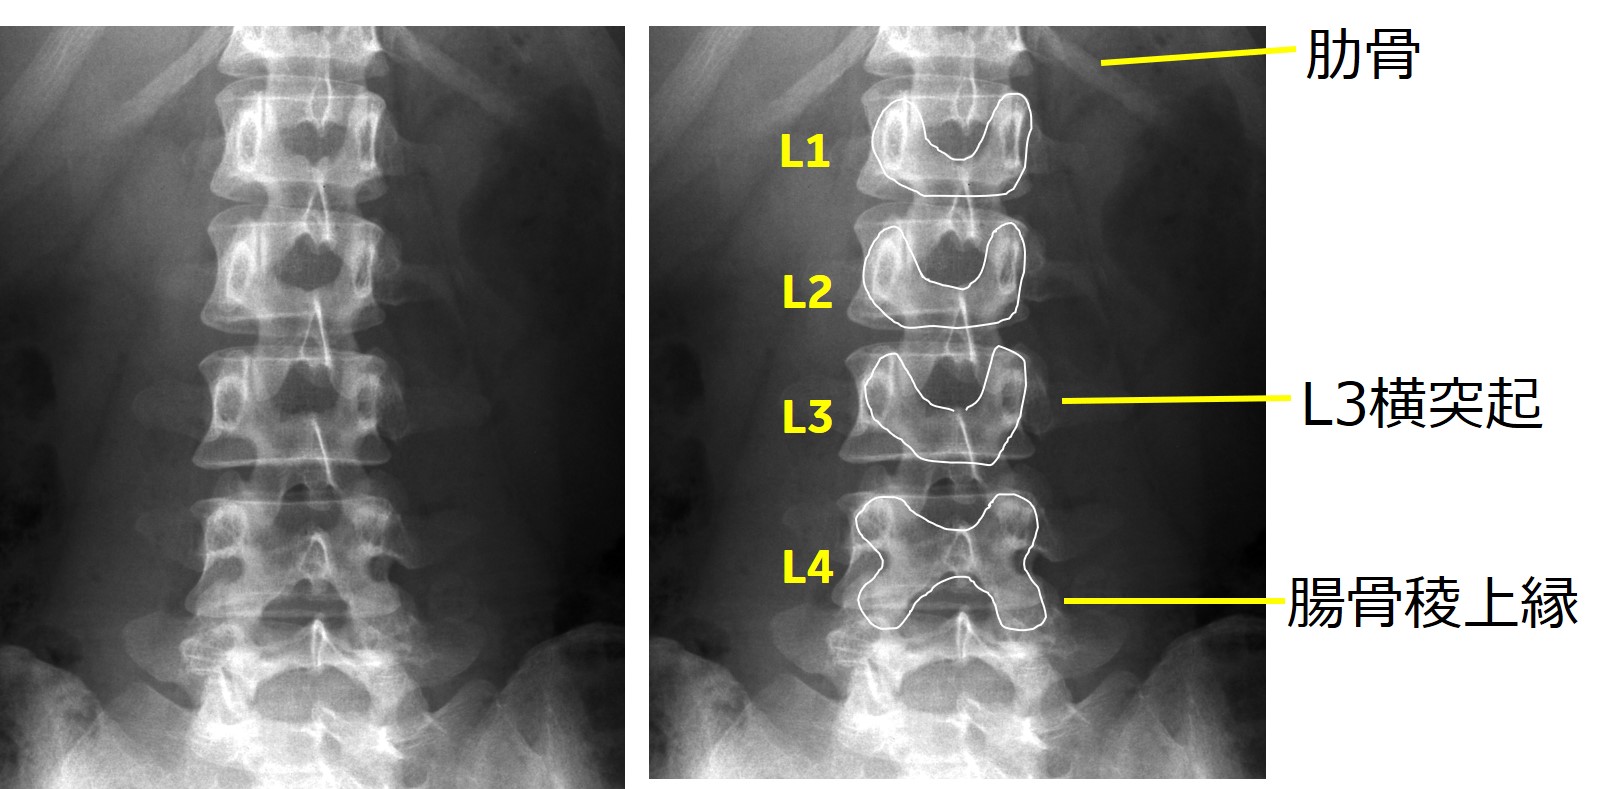

・基本的に、肋骨の同定と腸骨稜を確認して、椎体レベルを決めます。そのほかに有用な手がかりは、最も長い横突起はL3であること、L1-L3の後方成分はU字型であるが、L4はX字型などが参考になる(図4)。

ClinicalTips03_05.jpg

図4. 各椎体の有用な手がかり